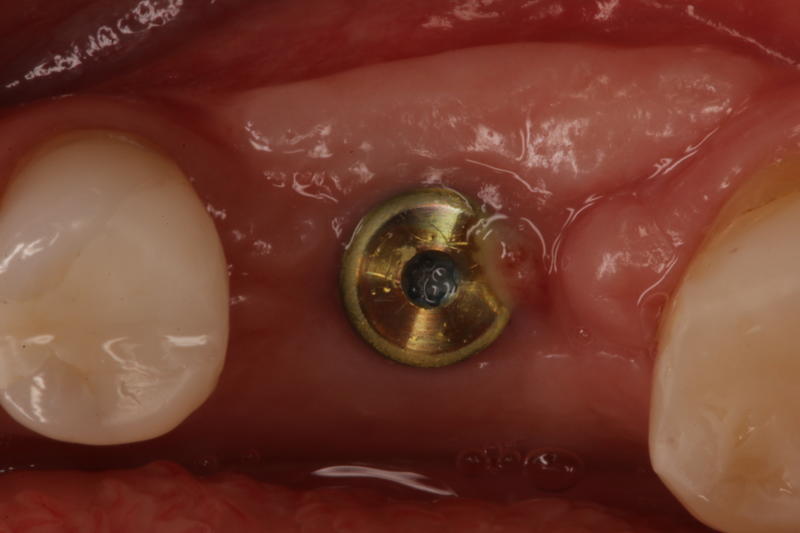

How to handle the infection?

Learn the steps to not only remove the infected implant, but also rebuild the site